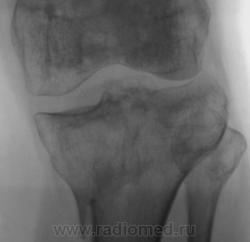

Консолидированый перелом проксимального эпифиза большеберцовой кости с повреждением наружного мениска и крестообразных связок ( вернее после их пластического восстановления ).

Александр Викторович,стояние отломков можно считать удовлетворительным?.+ вторичный ДОА+"пятнистый" остеопороз с участками остеосклероза.

стояние отломков, по истечении года, большого значения уже не имеет, главное что консолидация наступила, связочный аппарат восстановлен, в данном случаи нужно оценивать функцию, опорность, объем движений в данном суставе. Хотя внутренний мыщелок б\б кости просел прилично...